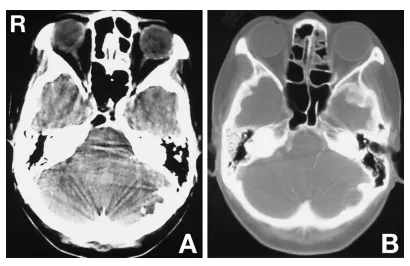

计算机断层扫描(CT)显示左侧后颅窝内板处存在伴钙化的低密度肿块(图2A)。骨窗CT显示颅骨内板受侵蚀(图2B)。钆增强T1加权磁共振成像显示板障内部分呈低信号伴环形强化,小脑内部分呈低信号(图3A)。T2加权磁共振成像显示硬膜外部分呈高信号,硬膜下部分呈高信号并延伸至小脑(图3B)。